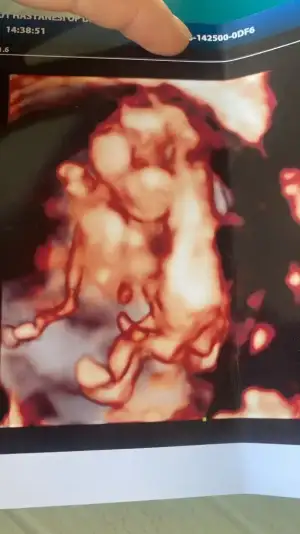

Merhaba hanımlar tabiki her şeyin başı sağlık ama her anne gibi merakla beklemek çok heyecanlı ve sabır gerektiren bir durum sadece merak 12 haftalık gebeyim dr hiç bir cinsiyet tahmininde bulunmuyor eee ben de merakımdan sizlere tahmin sormak istedim